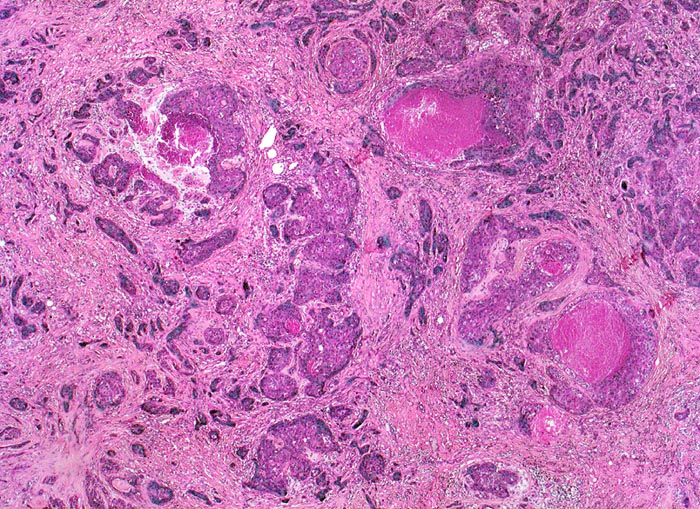

wenig differenziertes invasives duktales Mammakarzinom

Das Karzinom bildet keine drüsigen Strukturen, sondern ausschliesslich solide Zellstränge mit infiltrativem Wachstum in desmoplastischem Stroma. Fokal sind Tumornekrosen erkennbar.

Das histologische Grading (G1 bis G3) der Mammakarzinome wird bestimmt aufgrund des Prozentualen Anteils von drüsigen und soliden Tumorarealen, der zytologischen Atypien und der Anzahl Mitosen. Diesen drei Komponenten wird ein Wert zwischen 1-3 zugeordnet und zu einem Score aufaddiert (B.R.E. Score).

Der vorliegende Tumor hat einen hohen Anteil solider Tumorareale, zeigt ausgeprägte Zellatypien und zahlreiche Mitosen entsprechend einem wenig differenzierten Karzinom.